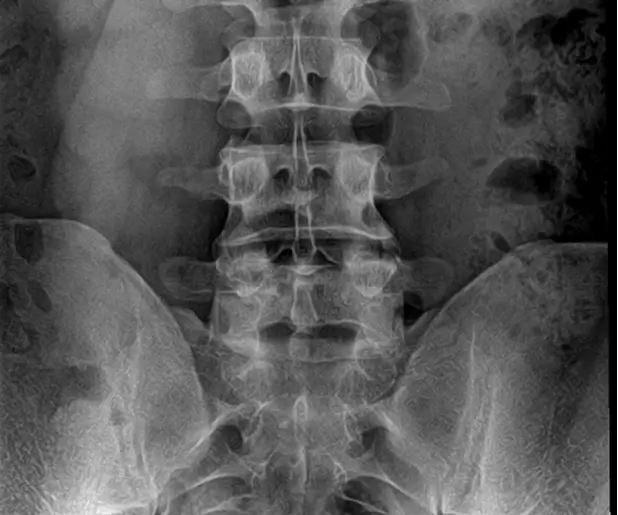

Pre OP radiographs, frontal and sagittal views